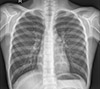

This sample image is for reference. Please only upload chest X-rays.

Uploading images other than chest X-rays or blurry/out-of-focus X-rays might show misleading results.